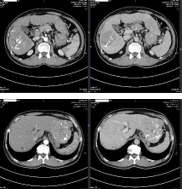

- CT scanner ngực-bụng: U gan đa ổ 2 bên phải và trái tính chất động học của HCC kích thước lớn nhất 7,9x10,4cm. Không có huyết khối tĩnh mạch cửa. Lồng ngực hiện không phát hiện tổn thương nghi thứ phát.

• Chẩn đoán xác định: UTBMTBG giai đoạn BCLC B – Xơ gan child A - VGB

• Phương pháp điều trị: Nút mạch hóa chất (Transcatheter Arterial Chemoembolization – TACE) + thuốc kháng virus Tenofovir 300mg/ngày

• Đánh giá đáp ứng:

| Trước điều trị | Sau TACE lần 1 | Sau TACE lần 2 |

Hình 1. Quá trình nút mạch khối u gan hai bên lần 1 |

Hình 2. Kết quả chụp CT bụng sau 1 tháng, khối u gan hai bên vẫn tăng sinh mạch nhiều |

| AFP: 99,5ng/mL AFP-L3: 14,3% Pivka-II: 8194mAU/mL | AFP: 347,8ng/mL AFP-L3: 35,0% Pivka-II: 6475mAU/mL | AFP: 1064,8ng/mL AFP-L3: 36% Pivka-II: 5089mAU/mL |

Bảng 1. Đánh giá đáp ứng điều trị sau 2 lần TACE chất chỉ điểm u tăng dần